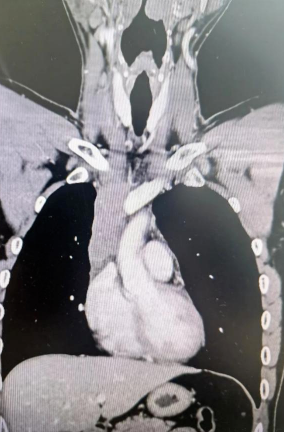

經(jīng)檢查發(fā)現(xiàn)患者前上縱隔腫瘤已經(jīng)完全侵犯了我們?nèi)梭w最主要的大靜脈之一——上腔靜脈,導(dǎo)致上腔靜脈回流嚴(yán)重受阻并導(dǎo)致由上腔靜脈起至左側(cè)無名靜脈、右側(cè)鎖骨下靜脈、右側(cè)頸內(nèi)靜脈等多根自上往下回流的靜脈阻塞,從而形成了廣泛的栓子,牢牢堵住了要流回心臟的血流,只能靠別的一些側(cè)支循環(huán)超負(fù)荷的工作,這也就是為什么孫先生脖子甚至是頭都明顯腫起來的原因。

4月30日,麻醉完成后,縱劈胸骨顯露右上縱隔腫瘤,發(fā)現(xiàn)腫瘤侵入上腔靜脈起始部,右鎖骨下靜脈及右頸內(nèi)靜脈血栓形成并向遠(yuǎn)端延伸。劉志主任團(tuán)隊將切口向右頸部延長,顯露右側(cè)頸內(nèi)靜脈至下頜角水平。張金洲副院長團(tuán)隊經(jīng)股動靜脈和左無名靜脈建立體外循環(huán)。在阻斷左無名靜脈遠(yuǎn)端后,李文海副院長團(tuán)隊完整切除縱隔腫瘤及部分上腔靜脈、左無名靜脈、右鎖骨下靜脈和右頸內(nèi)靜脈切除。張金洲副院長團(tuán)隊實(shí)施了無名靜脈近端、右鎖骨下靜脈和右頸內(nèi)靜脈內(nèi)血栓取出術(shù),并完成了左無名靜脈、右頸內(nèi)靜脈和右鎖骨下靜脈的人工血管置換手術(shù)。歷時6小時,三個外科團(tuán)隊在麻醉科柴偉主任團(tuán)隊、體外循環(huán)團(tuán)隊以及食管超聲和手術(shù)室協(xié)作下,手術(shù)獲得成功。

術(shù)后患者經(jīng)過心外監(jiān)護(hù)室和胸外監(jiān)護(hù)室的接力治療,目前患者恢復(fù)順利,顏面部腫消失。復(fù)查增強(qiáng)CT三條人工血管通暢。